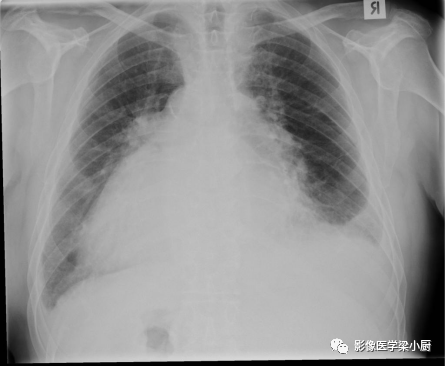

图片

急性肺水肿患者X线图像:双肺外野可见Kelery B 线(黑色箭头),为间质性水肿表现。双肺同样可见趋向于融合的结节性阴影(白色箭头),为肺泡性肺水肿表现。